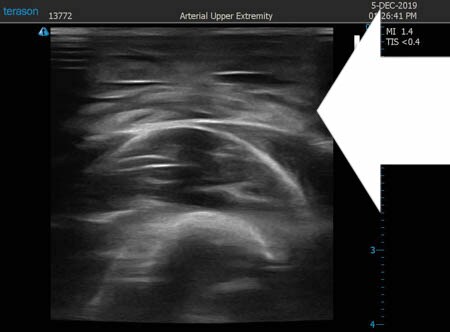

いつものように3Dタッチビュー(超音波)で

皮下脂肪層を評価してみましょう。

右二の腕

↓ ↓ ↓